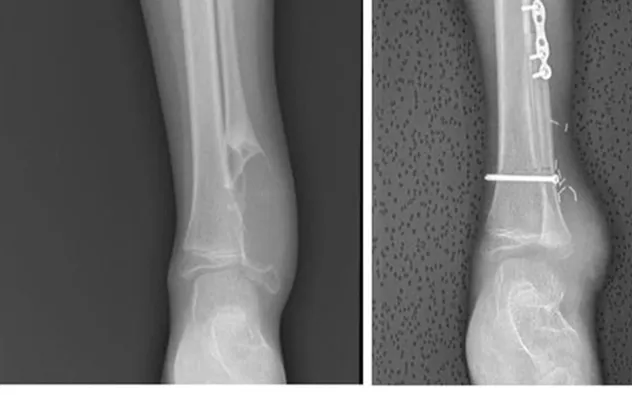

Ê-kíp quyết định áp dụng kỹ thuật ghép chỏm xương mác có cuống mạch, kết hợp vi phẫu nối mạch và tái tạo hệ thống dây chằng cổ chân. Ca mổ kéo dài 8 giờ, đòi hỏi sự phối hợp chặt chẽ của nhiều chuyên khoa và độ chính xác cao trong từng thao tác nhằm tránh tổn thương mạch máu, thần kinh.

Theo TS.BS Hoàng Hải Đức, việc tái tạo không đơn thuần là ghép xương mà phải khôi phục được cấu trúc chịu lực và độ ổn định của khớp cổ chân. Nếu thực hiện không đúng kỹ thuật, trẻ có nguy cơ lệch trục chi, hạn chế vận động và có thể phải can thiệp nhiều lần về sau.

Sau phẫu thuật, bệnh nhi hồi phục tốt, xương ghép ổn định, chức năng vận động và cảm giác bàn chân được bảo tồn. Hai tuần sau mổ, trẻ xuất viện và không cần hóa trị bổ sung.